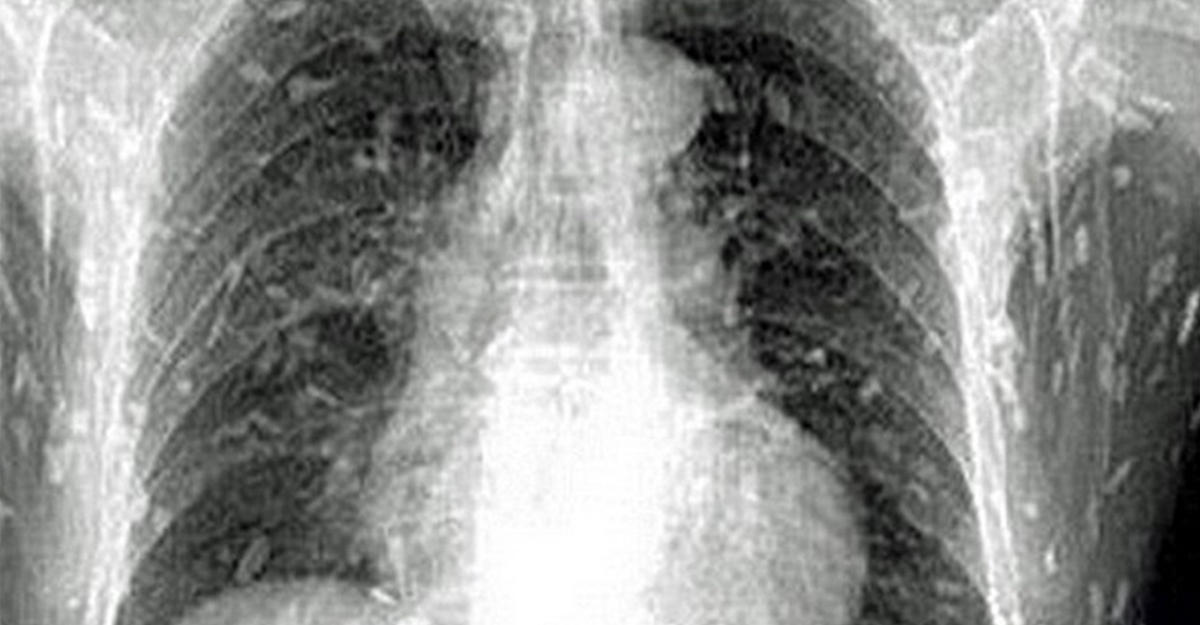

А все началось с того, что китаец пошел к доктору с жалобами на боли в животе и сыпь на коже, передает Day.Az со ссылкой на Soulpost.ru. К его ужасу, рентген показал, что все его тело заражено глистами - солитерами, ленточными червями.

Личинки солитера часто живут в пресноводной рыбе, такой как лосось, хотя иногда сохраняются даже в маринованной и копченой рыбе. Конечно, чаще всего это бывает в местностях с плохими санитарными условиями, но случается и в развитых странах.

Как отмечают врачи, виной всему большой спрос на суши, так что производитель все меньше обращает внимание на качество рыбы.